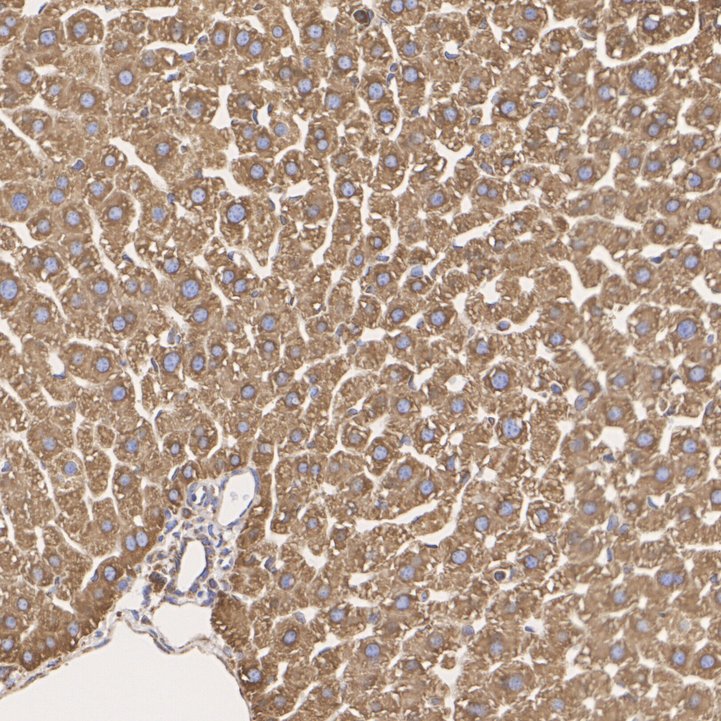

Catalog# M1506-2

GRP78 / BIP Mouse Monoclonal Antibody [C9-9]

IHC-P